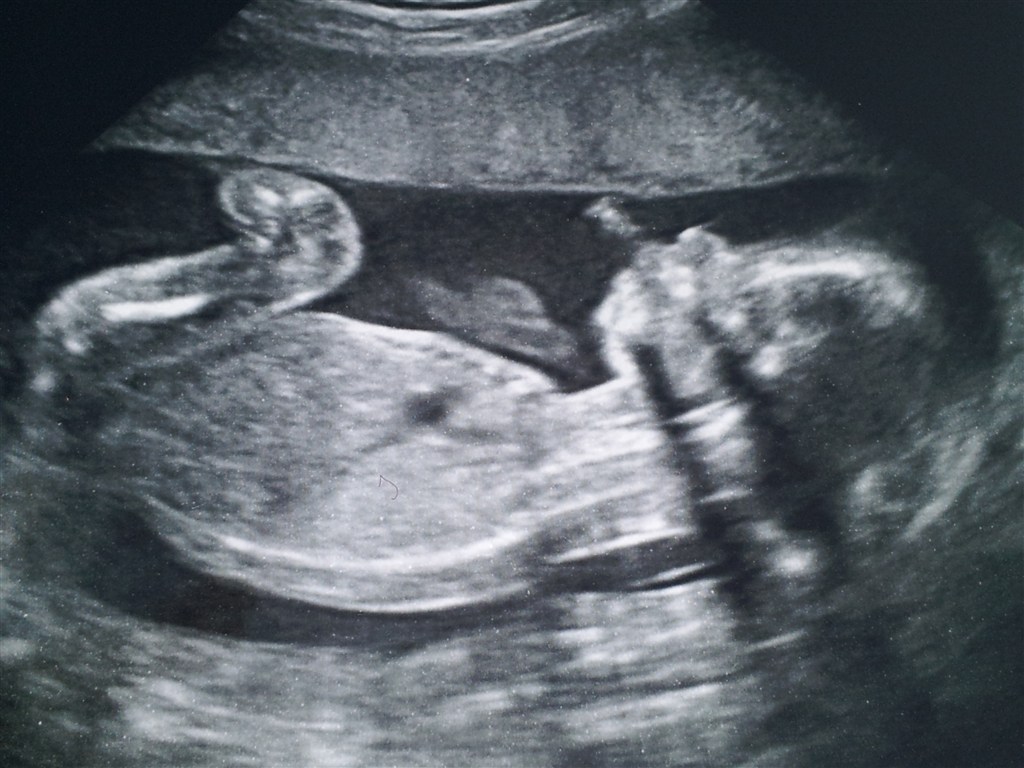

Det gik så godt til MD scanningen i dag! Vores lille baby er helt perfekt og MEGET aktiv.. Kan mor godt mærke på sin blære!

Lige et billede af vores dejlige put!